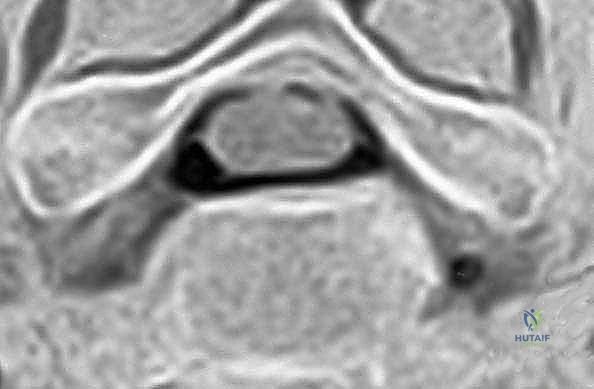

- التصوير بالرنين المغناطيسي (MRI): وهو الفحص الأهم لتحديد موقع الانزلاق الغضروفي بدقة ومدى انضغاط الأعصاب.

باستخدام أدوات ميكروسكوبية دقيقة، يتم تفريغ وإزالة القرص الغضروفي التالف بالكامل. يتم كشط الغضروف حتى الوصول إلى السطح العظمي للفقرتين العلوية والسفلية.

الخطوة 5: تخفيف الضغط العصبي (Decompression)

هذه هي المرحلة الأهم والأكثر حساسية. يقوم الجراح بإزالة أي نتوءات عظمية (Osteophytes) أو أجزاء من الغضروف الممزق التي تضغط على الأعصاب الشوكية أو الحبل الشوكي، مما يعيد للقناة الشوكية اتساعها الطبيعي.